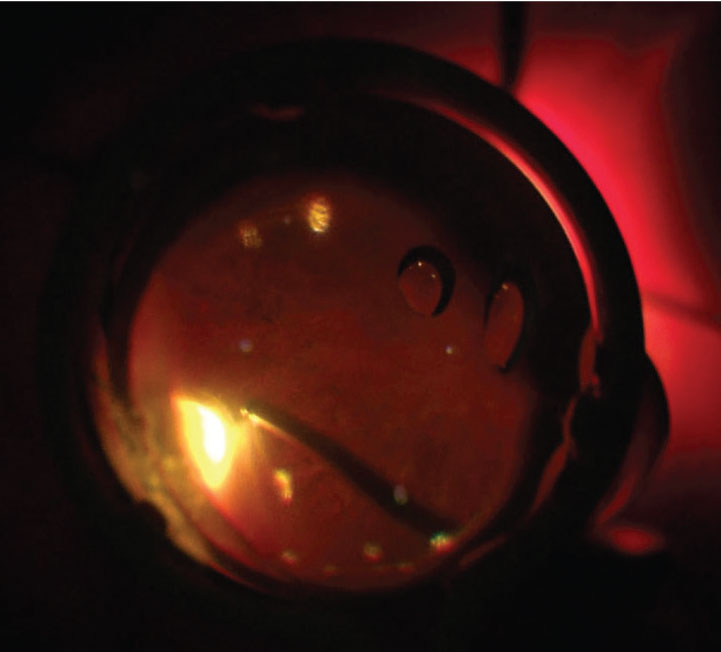

![]() |

| Figure 1. In scleral depression using a naked light pipe, the transilluminated scleral depressor provides enough internal light for safe vitrectomy and vitreous base shaving. |

The ability to visualize and work in the region of the vitreous base is an integral step of many vitreoretinal procedures. We typically do this by either depressing the sclera under chandelier illumination or having a surgical assistant perform the scleral depression.1

Recently, the use of lighted scleral depressors has become more commonplace. Many companies have produced guards that are placed over the light pipe, giving it properties that facilitate scleral depression. While using a smooth sleeve over the light pipe reportedly minimizes conjunctival trauma, we’ve found this step to be unnecessary and prohibitive from a cost-of-access perspective.

We reported on the use of a naked light pipe for transscleral depression,2 in which the shaft of an unguarded light pipe is placed parallel to the scleral surface until the end of the light pipe is over the area of interest (Figure 1). The light pipe shaft is then turned more perpendicular and depressed until the peripheral retina comes into view.

Subtle adjustment of the orientation of the light source may then highlight the anterior vitreous or retinal plane. This technique allows the surgeon to operate independently with maximum control.

We find this technique particularly useful for removing residual inferior vitreous hemorrhage or small residual particles of dislocated cataract that can be caught in the vitreous base. They’re are very nicely visualized with transscleral illumination.